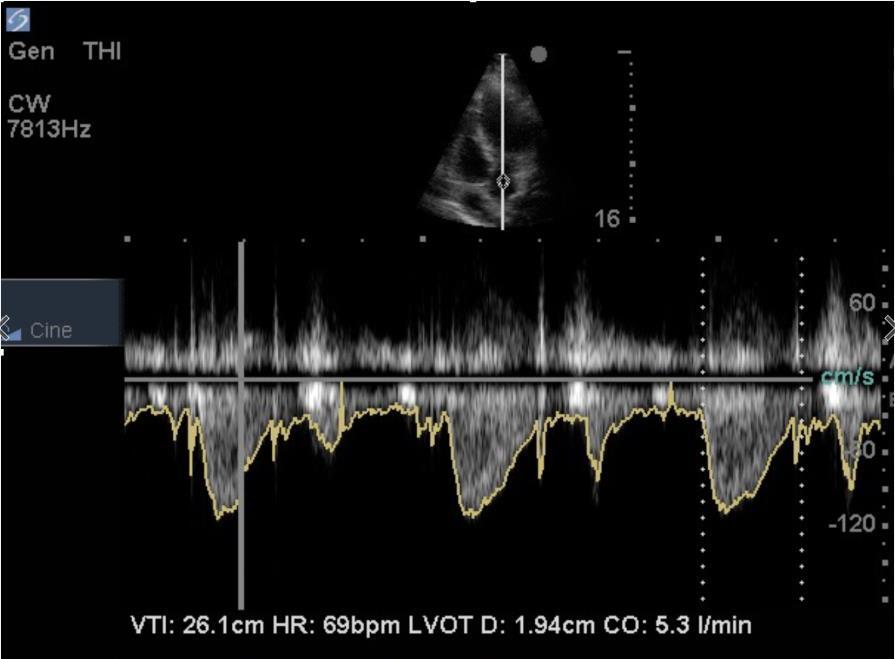

Heart Power Doppler or Continuous Wave Doppler through Aortic Valve Image